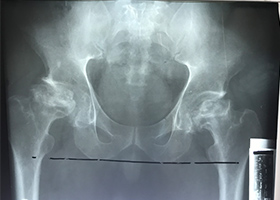

2 Year Follow Up Bilateral Hip Cambodia 2 Year Follow Up Bilateral Hip Cambodia 2 Year Follow Up Cambodia Bilateral Hip 2 Year Follow Up Cambodia Bilateral Hip 2 Year Follow Up Cambodia Bilateral Hip 2 Year Follow Up Cambodia Bilateral Hip